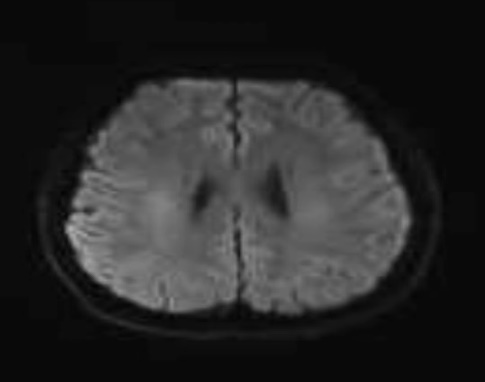

经过入院头颅核磁共振检查提示,小甘胼胝体、两侧内囊后肢、侧脑室体部及后角旁白质异常信号,经神经内科医生会诊后转至神经内科住院。

治疗前